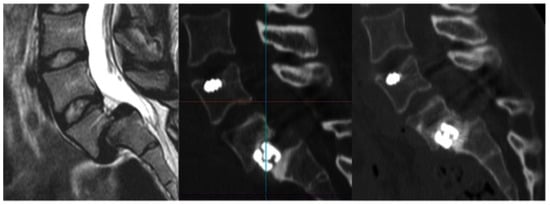

- Wolinsky, J.-P.; Sciubba, D.M.; Suk, I.; Gokaslan, Z.L. Endoscopic Image-Guided Odontoidectomy for Decompression of Basilar Invagination via a Standard Anterior Cervical Approach. J. Neurosurg. Spine 2007, 6, 184–191. [Google Scholar] [CrossRef] [PubMed]